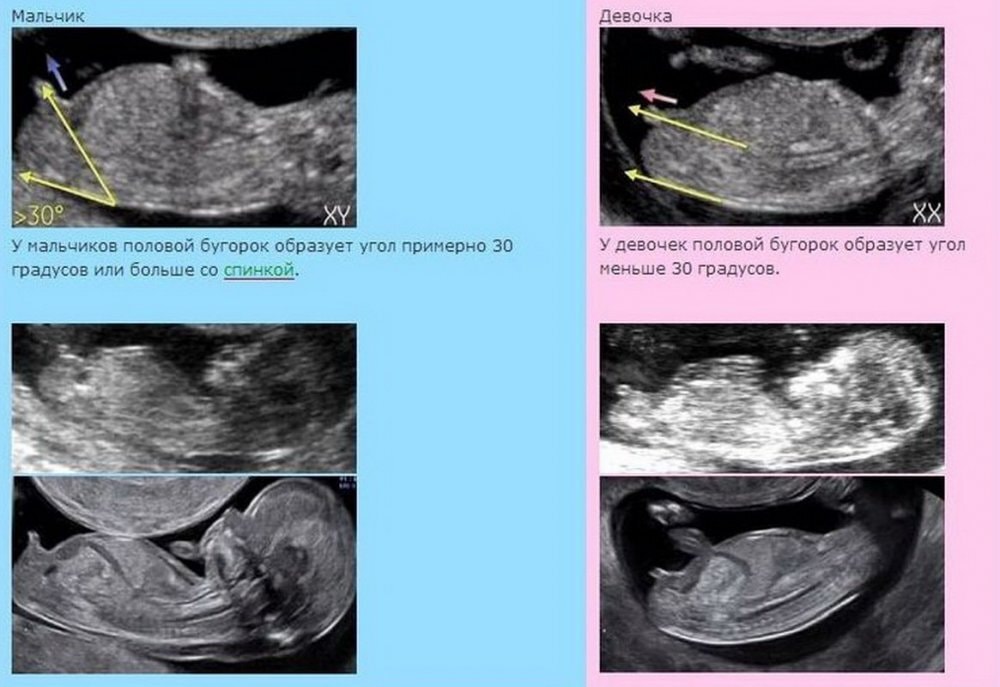

Пол по половому бугорку .

Ну если смотреть как обозначено в интернете, то получается девочка :) Изображение

Девочка, бугорок параллельно позвоночнику